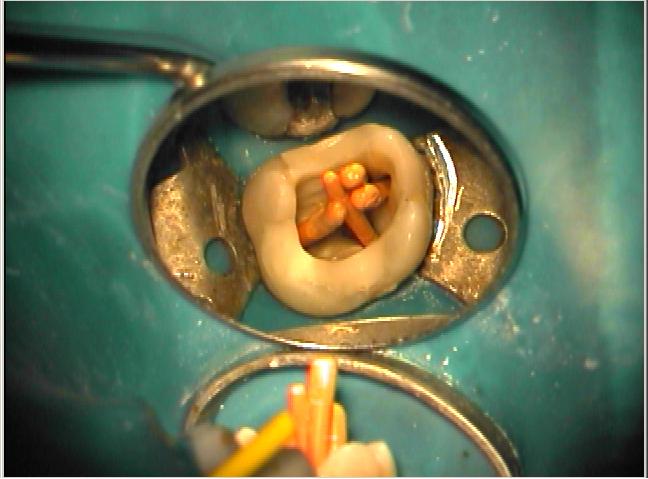

Klinische Situation nach abgeschlossener Aufbereitung

Vergrößerte Situation

Vergrößerte Situation; deutlich sind die 4 Kanaleingänge zu erkennen